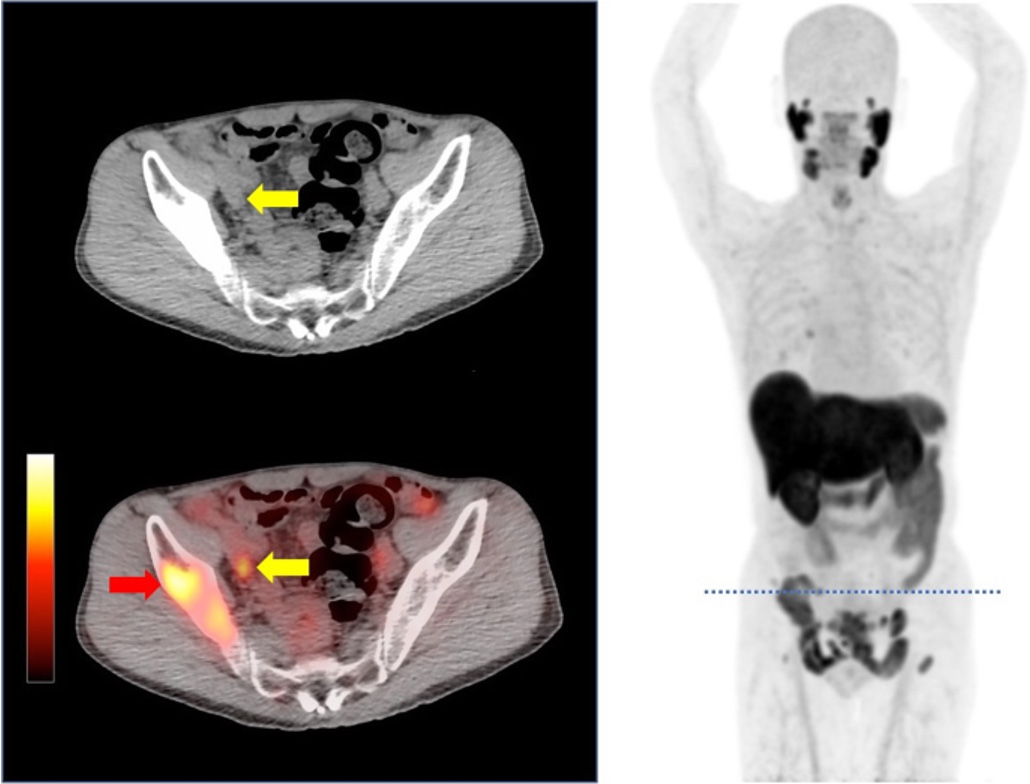

Targets PSMA to detect prostate cancer at staging and recurrence, delivering high‑contrast pelvic imaging.